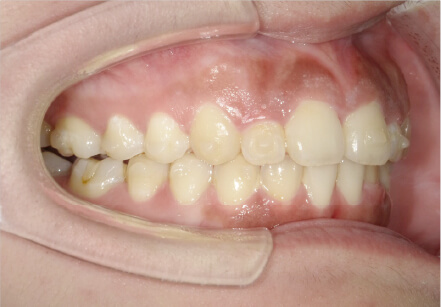

叢生の症例

41歳

/

女性

相談内容

横から見た時のガタガタが気になる

カウンセリング・診断結果

インビザライン、正中は上11に合わせていく、抜歯・拡大装置・IPR・アタッチメントOK

治療内容・方法

アライナー矯正

術後の経過・現在の様子

クリアライナー使用

治療のリスク

痛み・歯根吸収・歯肉退縮・虫歯・後戻り

費用・治療期間

880,000円、7ヶ月

トレーニングなど